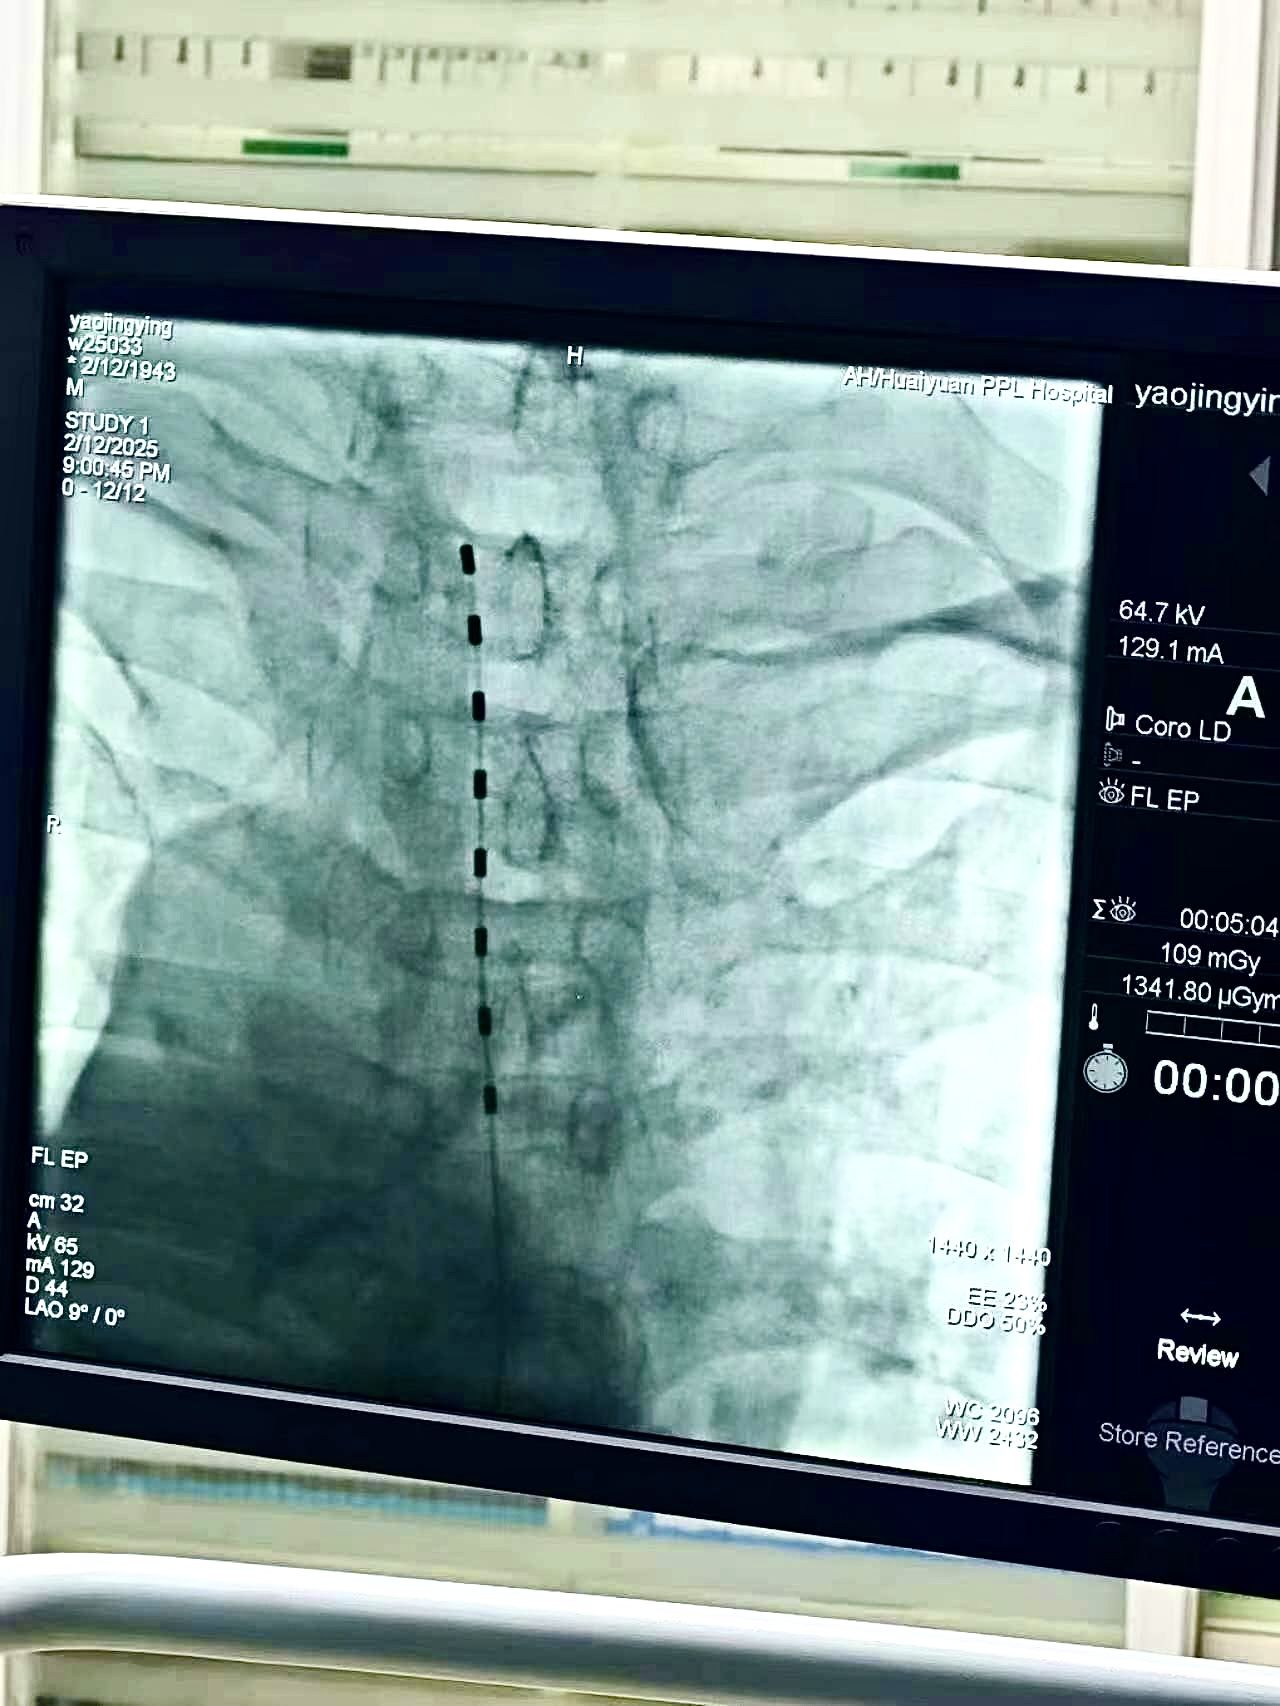

患者基础疾病多,疼痛科团队经过充分评估和考量,积极调整血糖血压、心功能,征得患者及家属同意,为患者制定了专业的治疗方案。2月12日下午在介入手术室,局部麻醉下为患者实施了脊髓神经电刺激植入术,手术历时90分钟。脊髓电刺激器被精准地置入患者的胸2脊髓平面。随着电流的轻轻刺激,那些曾经让患者痛不欲生的神经信号被有效抑制,患者的疼痛,就这样奇迹般地消失了。患者术前疼痛VSA评分8-9分;术后3天连续疼痛VSA评分2-3分,基本恢复了正常生活。